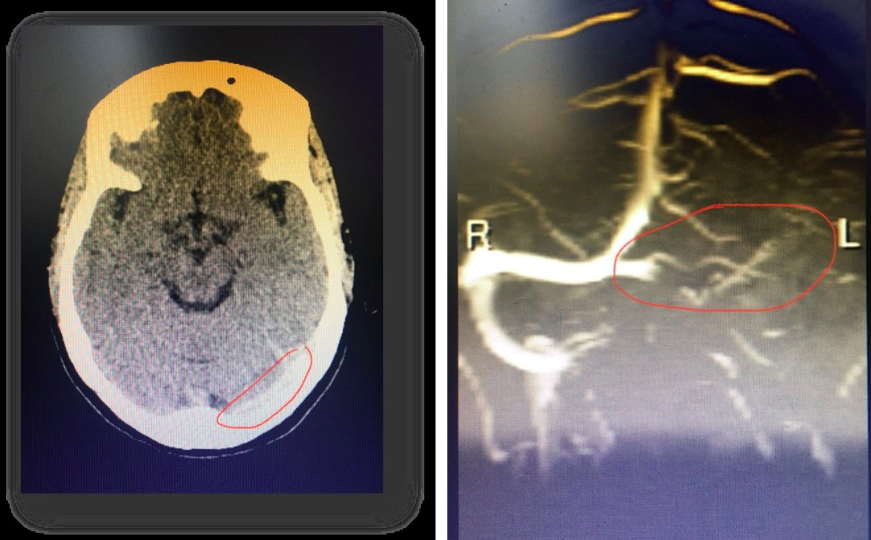

Ngày 20/3, bác sĩ chuyên khoa 1 Lê Hùng Dũng, Phó Trưởng khoa Tâm - Thần kinh, Bệnh viện Đa khoa tỉnh Hòa Bình, cho biết nữ bệnh nhân 47 tuổi được chụp cắt lớp vi tính sọ não, có hình ảnh dải tăng tỷ trọng nhu mô vùng chẩm bên trái.

Kết quả chụp cộng hưởng từ não - mạch não cho thấy bệnh nhân bị tắc hoàn toàn xoang tĩnh mạch ngang bên trái. Sau khi được điều trị, sức khỏe người phụ nữ này đã ổn định, không gặp di chứng.